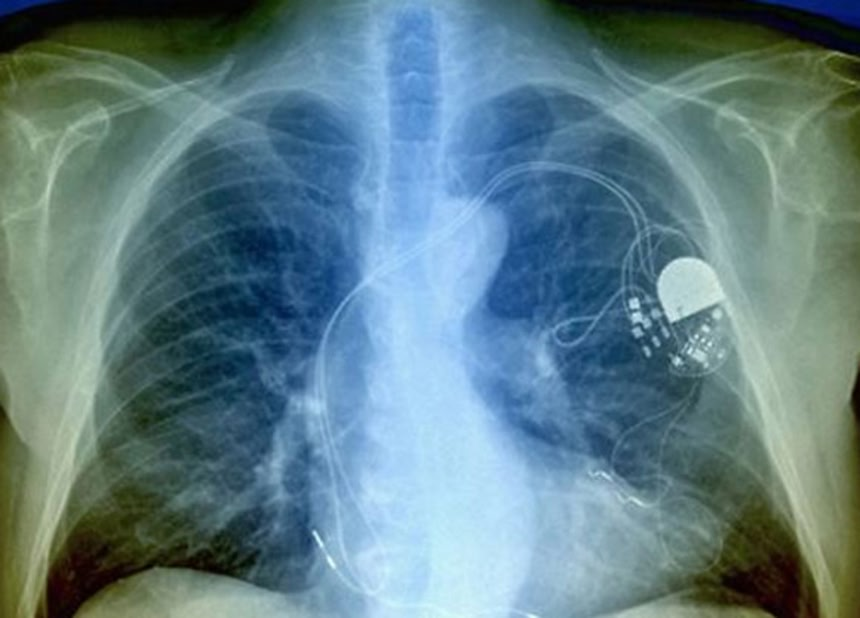

この画像を大きなサイズで見るインスリンのポンプや埋め込み式除細動器、ペースメーカーなどのように、ワイヤレスで電池式の医療機器は外部からハッキングすることが可能だ。2011年、ラスベガスで開かれた安全保障会議で、ハッカーのジェローム・ラドクリフが、自身のインスリンポンプにハッキングしてみせた。さらに数年前、ペースメーカーにもハッキングしたハッカーがいた。

これまで、人体に埋め込まれた医療機器が悪意をもって改ざんされたケースが詳しく報告されたことはないが、こうした危険も起こり得るという意識から、アメリカの政府系監視機関である政府説明責任局が、食品医薬品局から各医療会社に医療機器のこうした脆弱性を排除するよう要請する運びとなった。